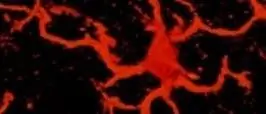

Что был бы нерв для бедняги, если бы не армада глиальных клеток в помощь! Именно эти вспомогательные клетки центральной нервной системы и превращают нерв в нерв: клетки олигодендроглии создают изолирующий миелиновый слой вокруг нейронов, тем самым обеспечивая молниеносную передачу возбуждения по нервной системе. Звездчатые астроглиальные клетки со своей стороны поддерживают передачу сигналов между отдельными нервными клетками, а также выполняют ряд других задач - например, помогают при детоксикации центральной нервной системы.

Очистка и удаление вторгшихся микроорганизмов является в первую очередь задачей третьего типа глиальных клеток, микроглии. Клетки микроглии становятся активными при повреждении нервов, воспалении участка центральной нервной системы или проникновении в него бактерий или вирусов. Затем активированные клетки микроглии набрасываются на умирающие клетки как клетки-мусорщики и уничтожают их.